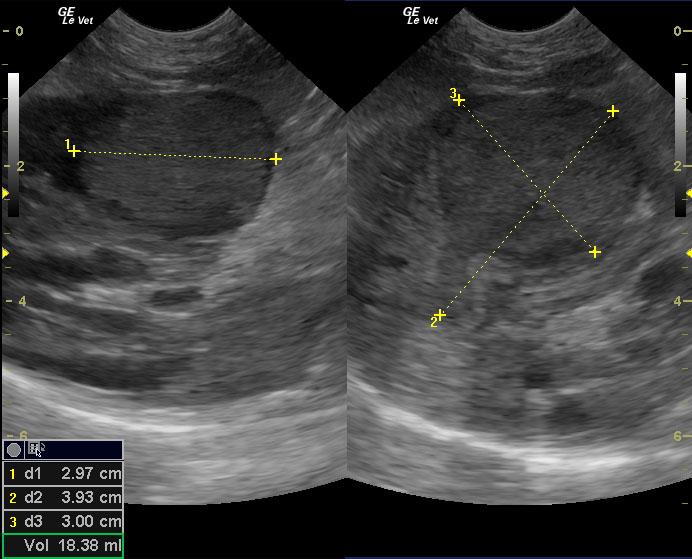

A 10-year-old, SF DSH cat was presented for acute onset vomiting and dehydration. Abnormalities on physical examination were icterus and dehydration. Pyuria with low urine SG was present on urinalysis. Urine culture was negative for bacterial growth after 24hrs. CBC and serum biochemistry showed marked leukocytosis with left shift and azotemia. Diffuse intestinal ileus was evident on survey radiographs.